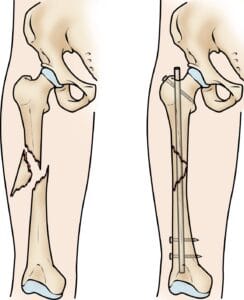

(Left) An oblique fracture has an angled line across the shaft. (Right) A comminuted fracture is broken into three or more pieces.

The main types of femoral shaft fractures include:

- Transverse fracture: Characterized by a horizontal break across the femoral shaft.

- Oblique fracture: Defined by an angled line running through the shaft.

- Spiral fracture: The break wraps around the shaft in a spiral pattern, often caused by a twisting force.

- Comminuted fracture: The bone is broken into three or more fragments.

- Open fracture: When bone fragments break through the skin or are exposed due to an external wound. Open fractures can cause extensive damage to muscles, tendons, and ligaments and carry a higher risk of complications, including infections, which may slow the healing process.